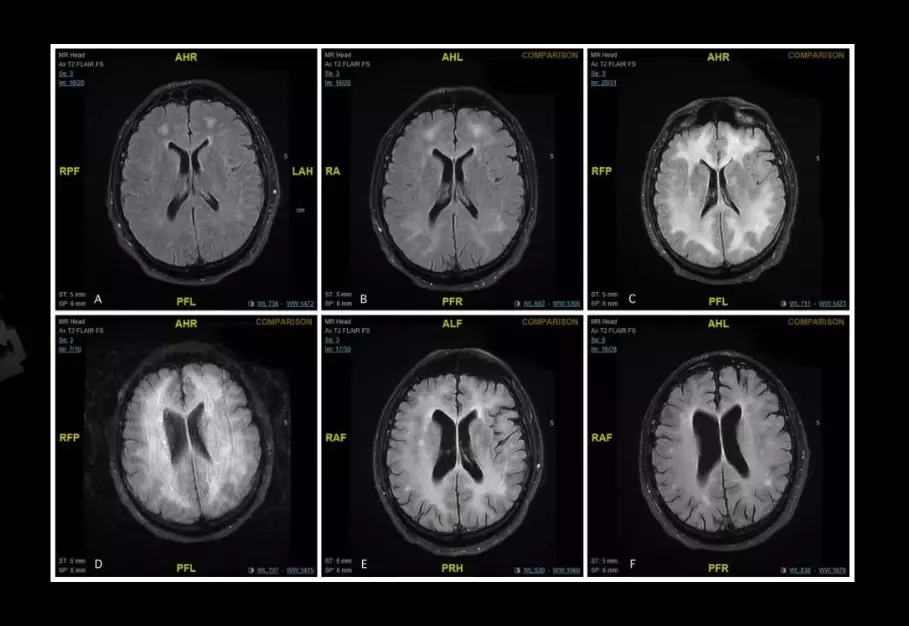

Images have been released that show the effects of cocaine on the human brain and the damage that the Class A substance can do in a very short amount of time.

The brain scans show how cocaine can 'eat away' at the brain, sometimes leaving the user with disabilities and - in extreme cases - dead.

The patient from whom the scans were taken was suffering from a rare but severe side-effect of cocaine use called cocaine-induced toxic leucoencephalopathy.

The white matter in his brain was discovered to have been damaged, which led to their diagnosis.

Four months later, his recovery was so successful that he was allowed home. In the intervening year, he has stayed clear of drugs and his yearly follow-up showed that while there were still 'persistent white matter changes' in his brain, neurological tests were normal.